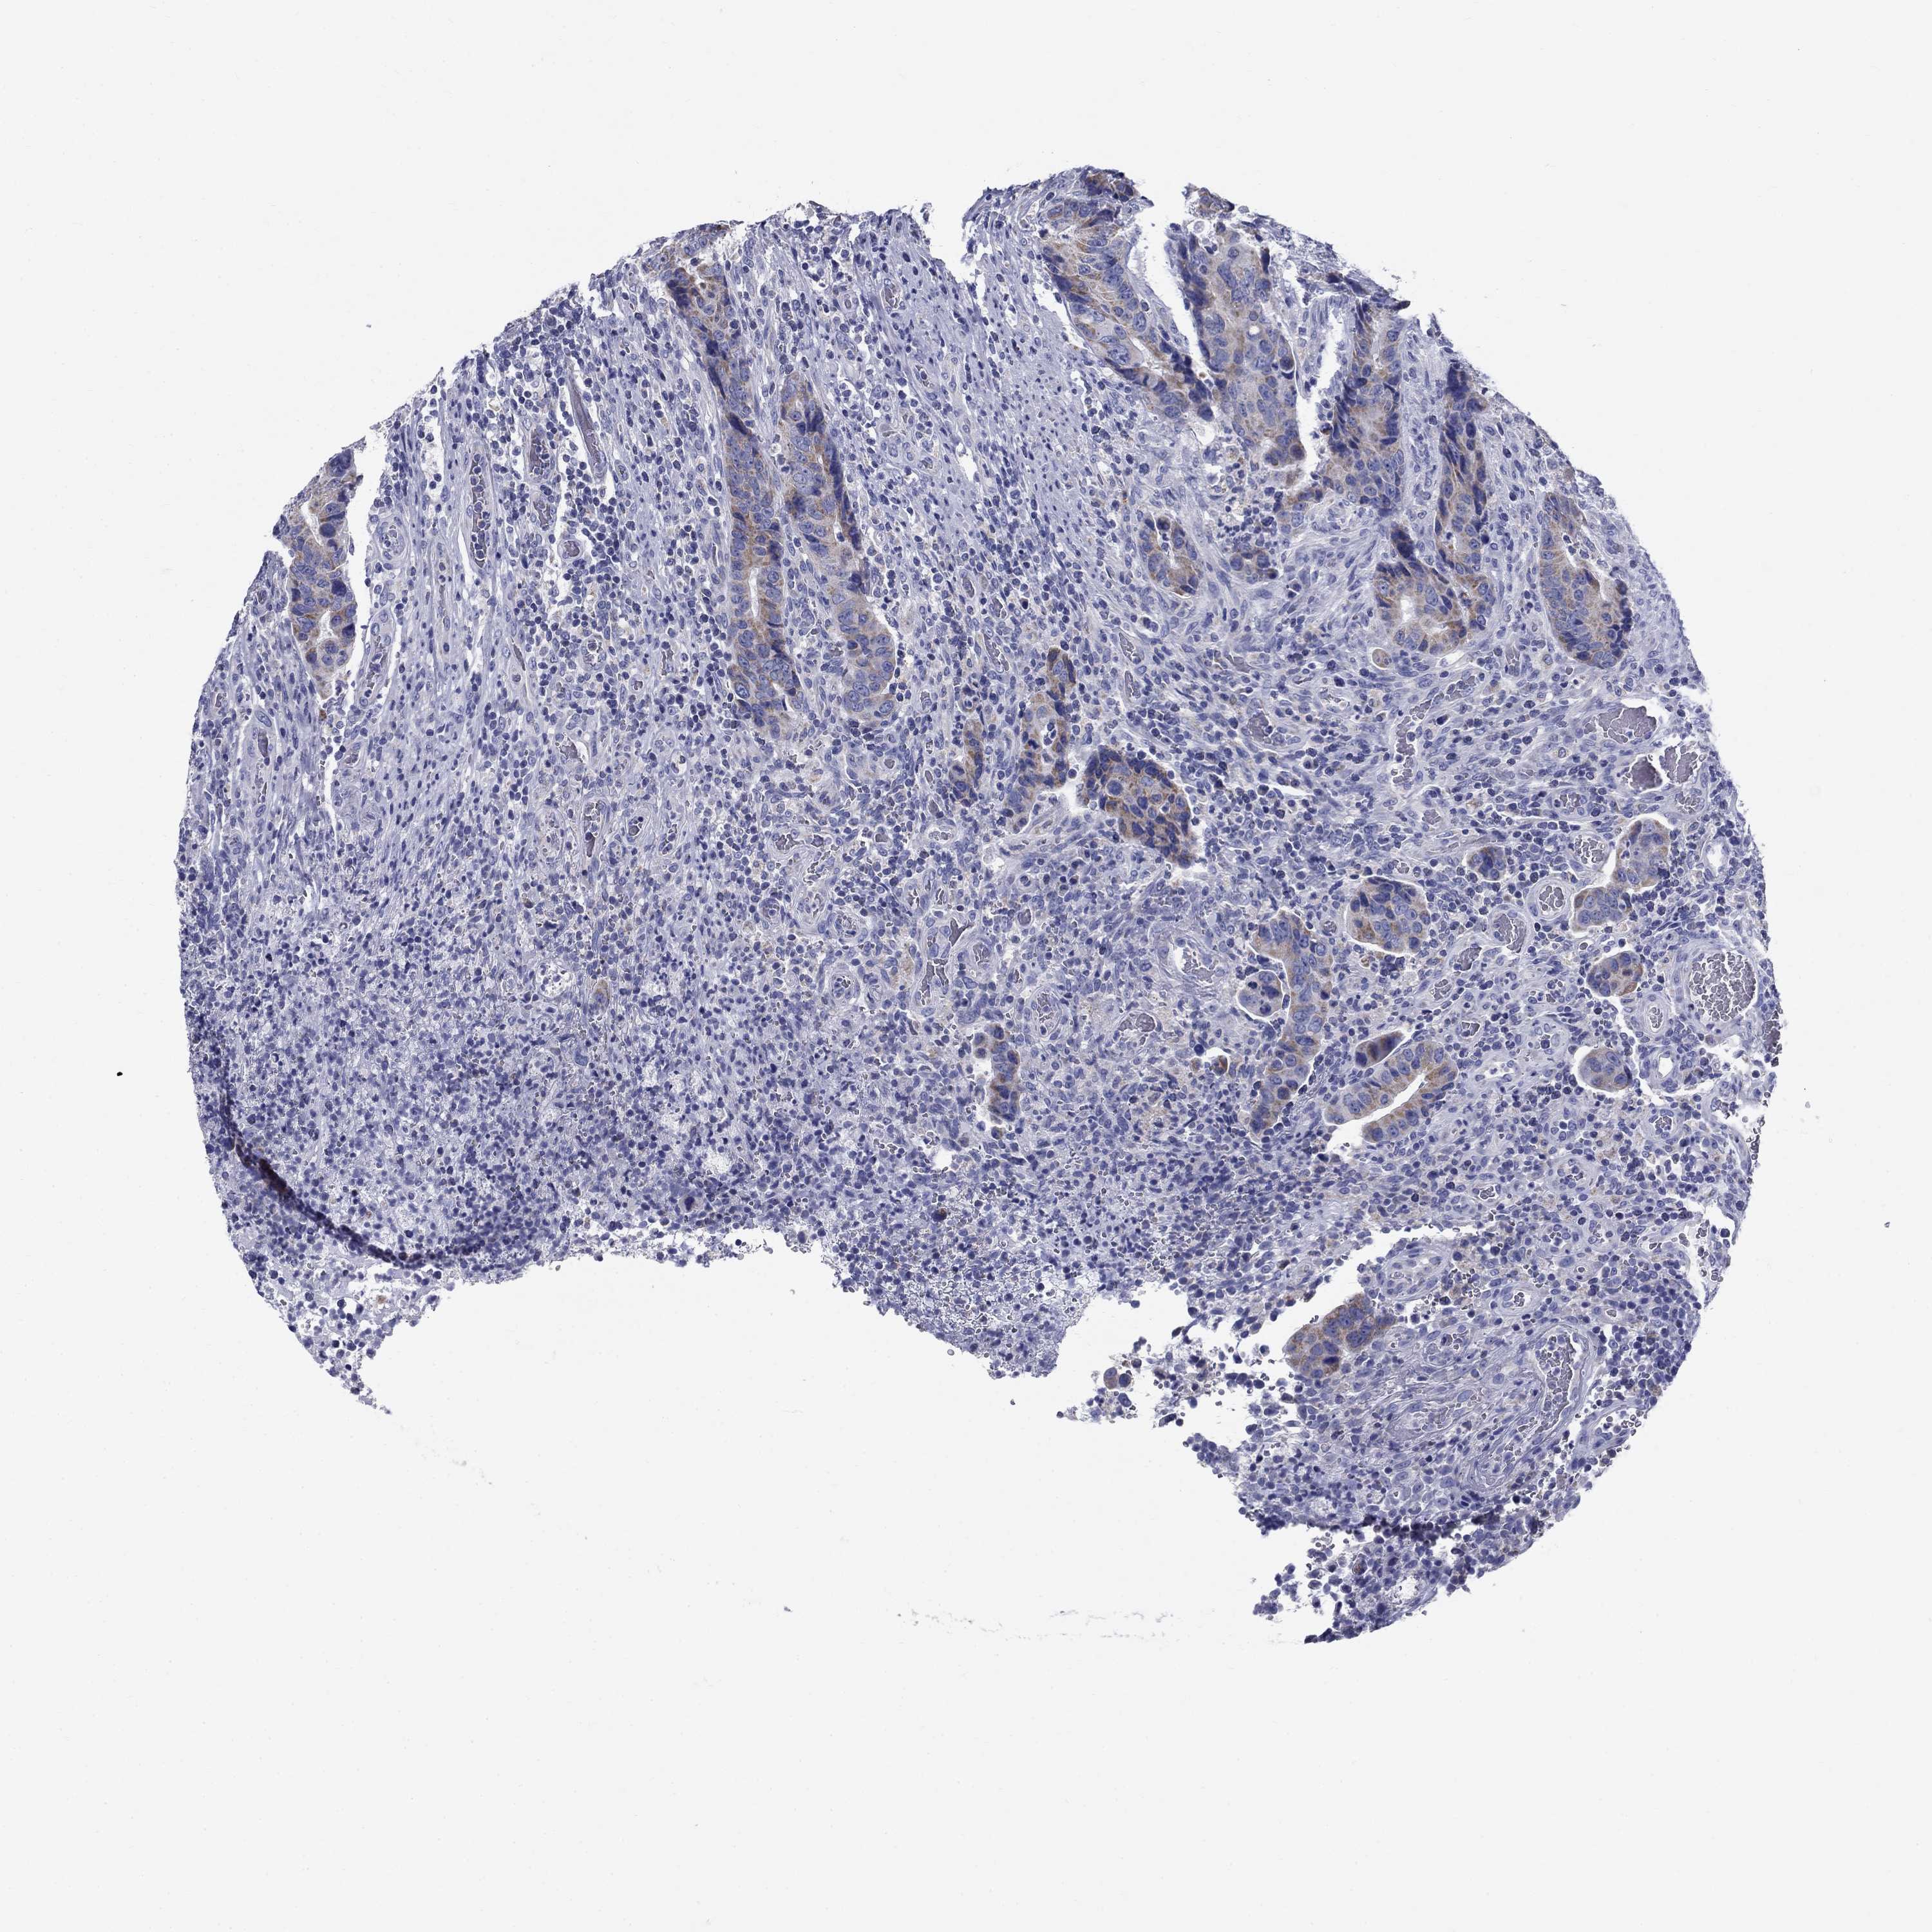

CANCER COLORECTAL CANCER Show tissue menu

Colorectal cancer

Human cancer

Colon adenocarcinoma